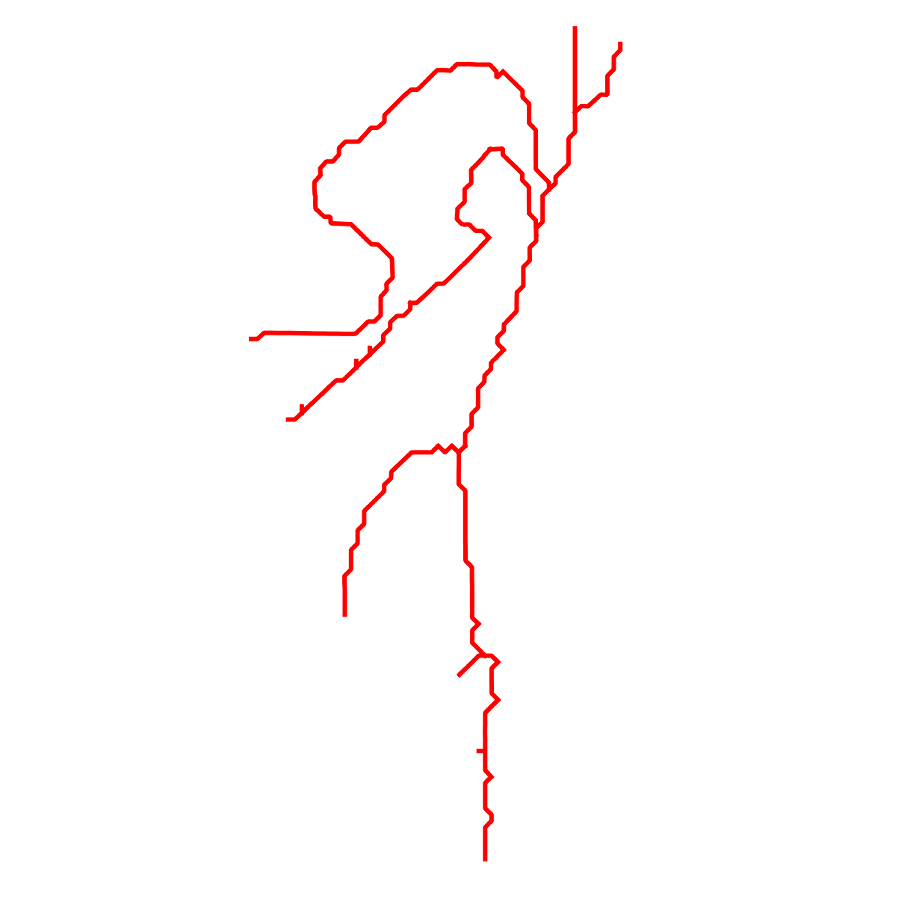

Fig. 3 shows the connectedness of vessels recovered from state-of-the-art vascular enhancers and curvilinear ridge detectors FFR and OOF together with the proposed CVM for the synthetic HCP and the real PC images.

On the synthetic phantom, FFR shows a fragmented and rough vesselness response in correspondence of irregularly shaped sections of the structure. Also, the response at the bifurcation is not smoothly connected with the branches (triangular loop). Conversely, OOF recovers the phantom connectedness at the branch-point, and the vesselness response is consistent along the tortuous curvilinear section, however ghosting artifacts are observed as the shape of the phantom becomes irregular (C-like) or differs from a cylindrical tube. Also, close convoluted structures, which change scale rapidly in the HCP, produce inconsistent responses of OOF (fig. 3). CVM shows here a strongly connected vesselness response in correspondence of both regular and irregular tubular sections, with local maxima at structures’ mid-line. The connectedness of the structures is emphasized regardless the complexity of the shape, and it resolves spatially the tortuous curvilinear ‘kissing vessels’ without additional ghosting artifacts, despite the smooth profile.

Similar results are observed on the PC dataset: FFR has a poor connected response in the noisy and low-resolution image. Vessels are overall enhanced, however thin and fragmented structures remain disconnected. Overall, the vesselness response is not uniform within the noisy structures, where maximal values are often off-centred. A more consistent response is obtained from OOF, where the connectedness of vessels is improved. Maximal response is observed at the mid-line of vessels, however, noise rejection is poor. CVM strongly enhances here the vessel connectivity. The fragmented vessels of PC have a continuous and smooth response in CVM with higher values and a more defined profile. Large vessels shows solid connected regions with local maxima at mid-line as in OOF. Conversely from OOF, CVM shows improved noise rejection in the background.

The respective tensor fields (TF) synthesized on both HCP and PC show consistent features. The TF’s characteristics are in line with the connectedness of CVM: enhanced and connected vessels are associated with high anisotropy, whereas background areas show a predominant isotropic component.